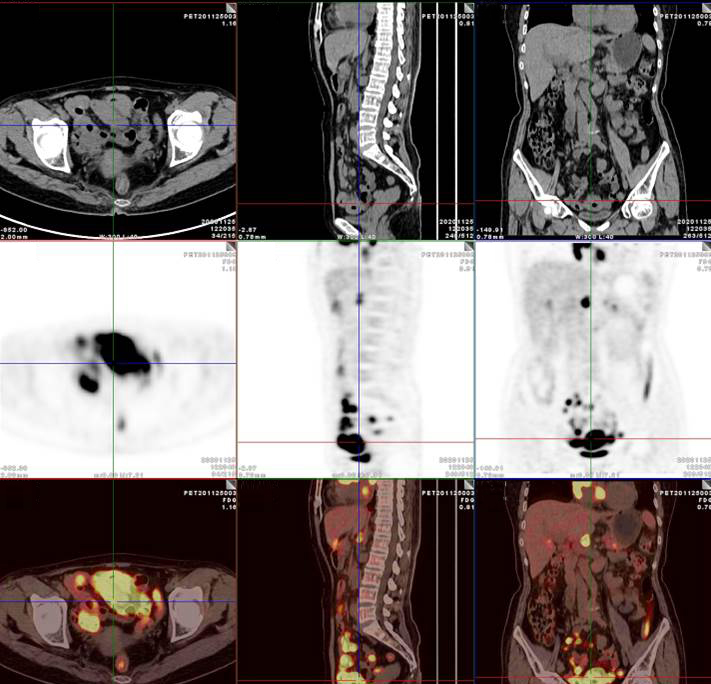

腸系膜多發(fā)淋巴結(jié)放射性攝取增高

多段小腸腸管放射性攝取增高